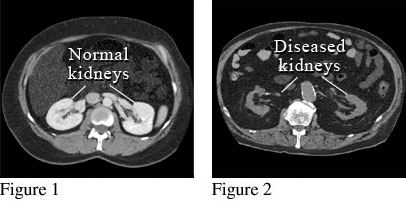

CT scan showing normal kidneys and damaged kidneys

Courtesy of Intermountain Medical Imaging, Boise, Idaho.

Figure 1 shows a picture of a computed tomography (CT) scan of two normal kidneys, looking from the top of the head down. A special dye (contrast material) was used for this scan. Figure 2 shows a picture from a different CT scan of two kidneys that are abnormal. These kidneys are small and misshapen from scarring due to disease.